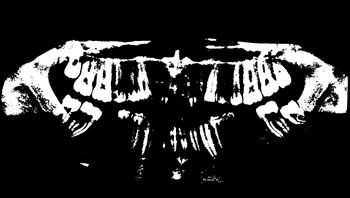

Figure 5: Determining the ROI of the images.

Determining ROI

For each image, after the annotation of the teeth, the buccal region was also annotated, covering the whole region delineated by the contour of the jaws. This process was carried out in view of preserving the area containing all the teeth (objects of interest). Finally, the region of interest (ROI) was determined by multiplying the values of the pixel array elements, representing the original panoramic X-ray image, by its corresponding binary matrix, resulting from the process of oral annotation. Figure 5 illustrates the whole process to determine the ROI of the images.